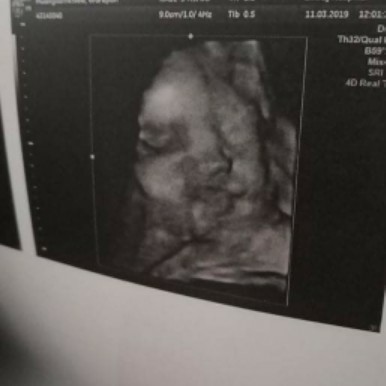

เพิ่งซาวด์วันนี้เลยค่ะ ผู้ชายยย หน้าเหมือนพี่ชายเขามาก 😁